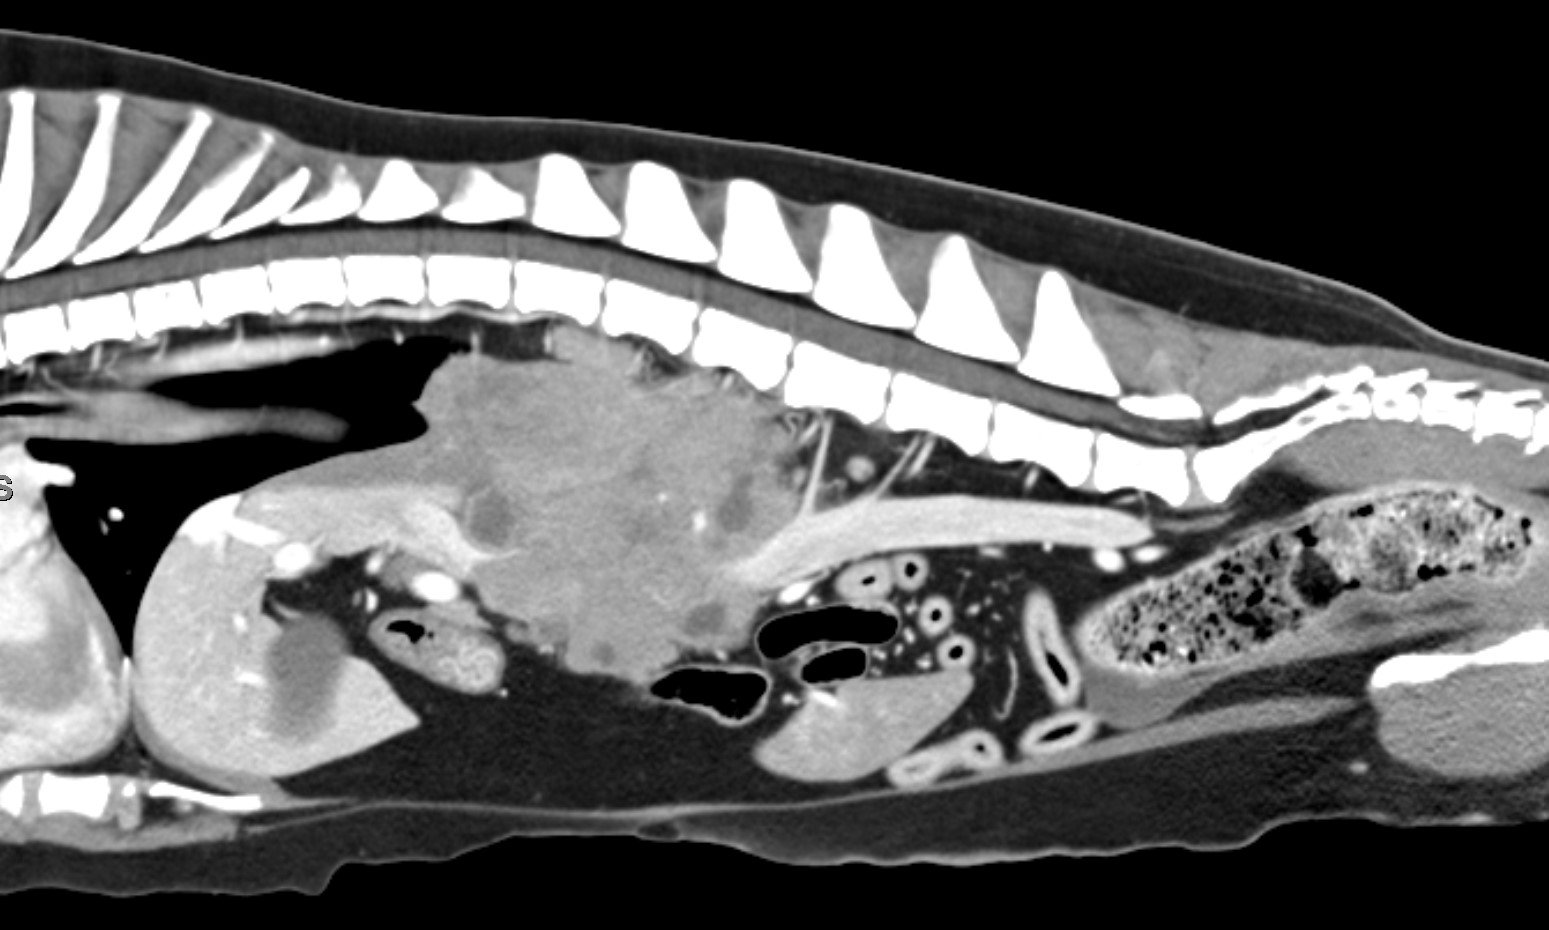

Ultrasound, Radiographs, CT, and MRI services provided by a board-certified veterinary radiologist.

Our mobile team comes to your practice and works with you to provide high quality results with diagnostic radiology services.